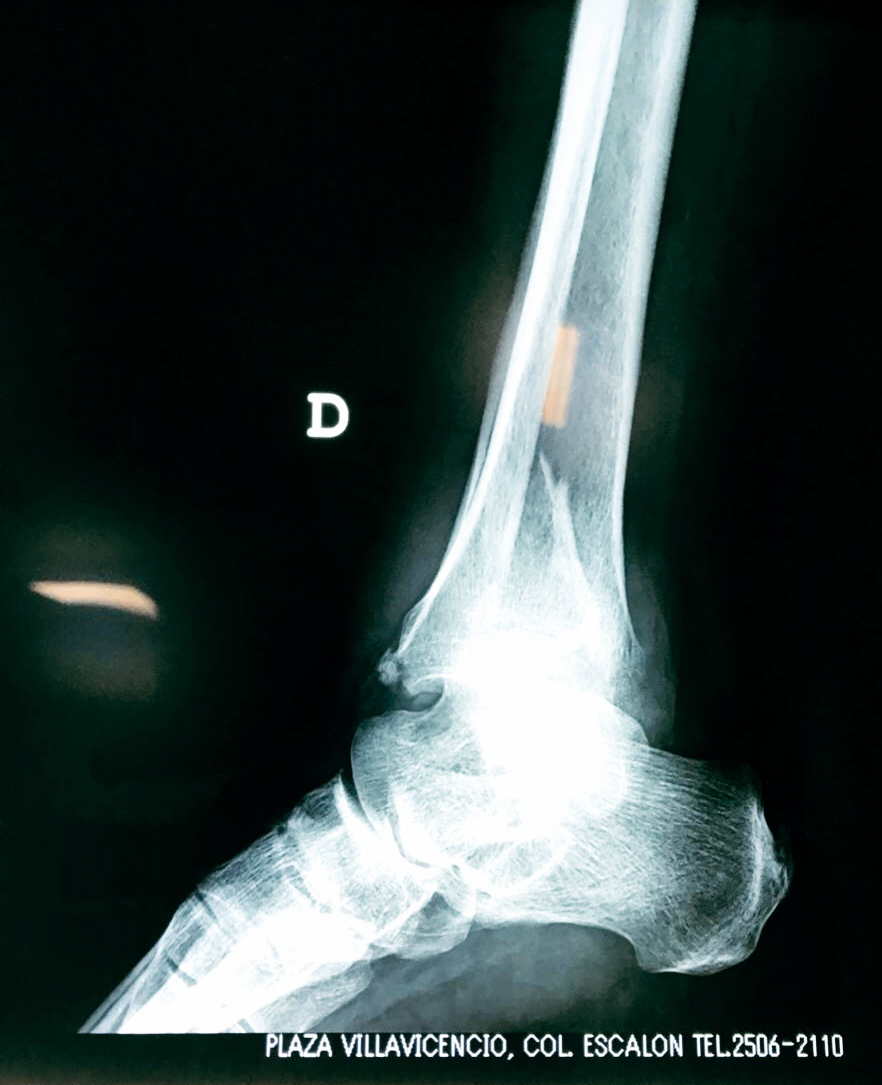

Algunas fracturas de tobillo pueden requerir cirugía si:

- Los extremos de los huesos están desalineados entre sí (desplazados).

- La fractura se extiende hasta la articulación del tobillo (fractura intra-articular).

Cuando se necesita cirugía, es probable que esta implique el uso de clavijas de metal, tornillos o placas para sostener los huesos en su lugar mientras la fractura se consolida. Los elementos de soporte pueden ser temporales o permanentes.